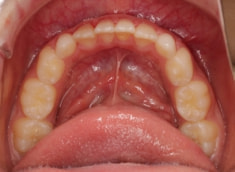

治療前